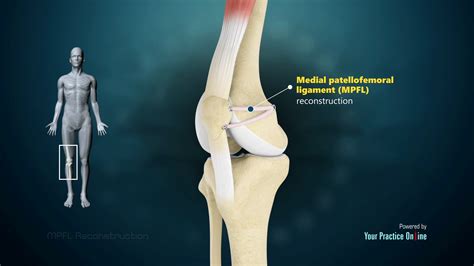

• MPFL Reconstruction: This procedure involves reconstructing the MPFL using a graft, typically from the patient's own tissue (autograft) or a donor (allograft). The graft is attached to the medial side of the patella and the medial femoral condyle to restore stability.

• Tibial Tubercle Osteotomy: This procedure involves realigning the patellar tendon by moving the tibial tubercle (the bony prominence on the tibia where the patellar tendon attaches). It is often performed in conjunction with MPFL reconstruction to address underlying malalignment issues.